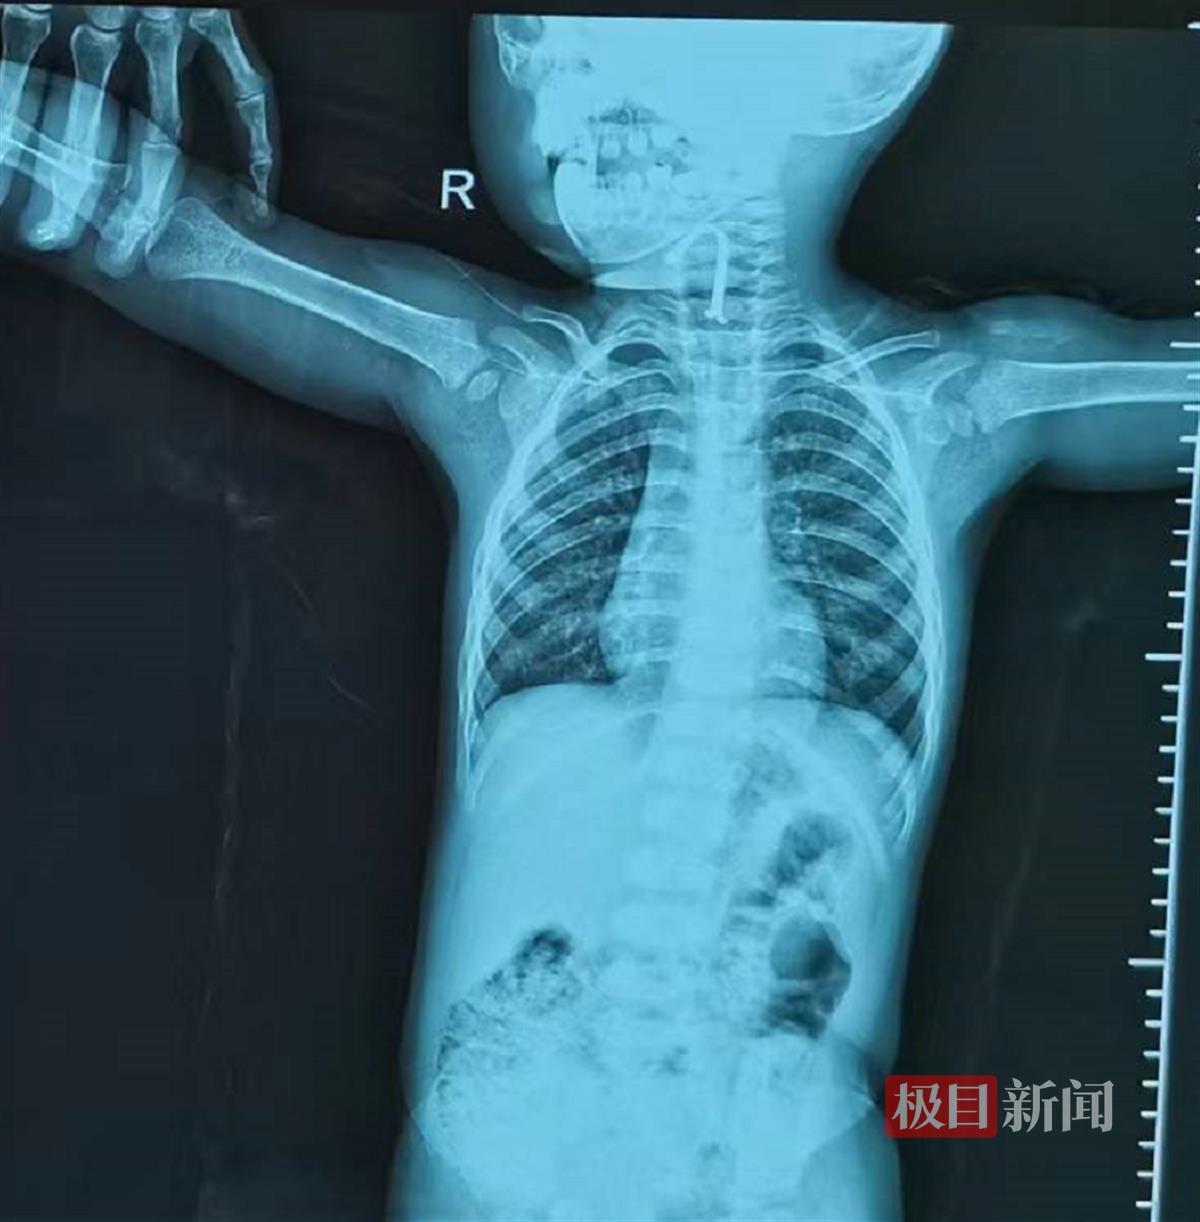

惊慌失措的家长赶忙将孩子送到武汉儿童医院,拍片发现有个不明金属物体卡在气管中间,当晚,耳鼻咽喉科医生急诊手术,用气管镜取出一个长约2厘米,宽7毫米LED发光二极管。